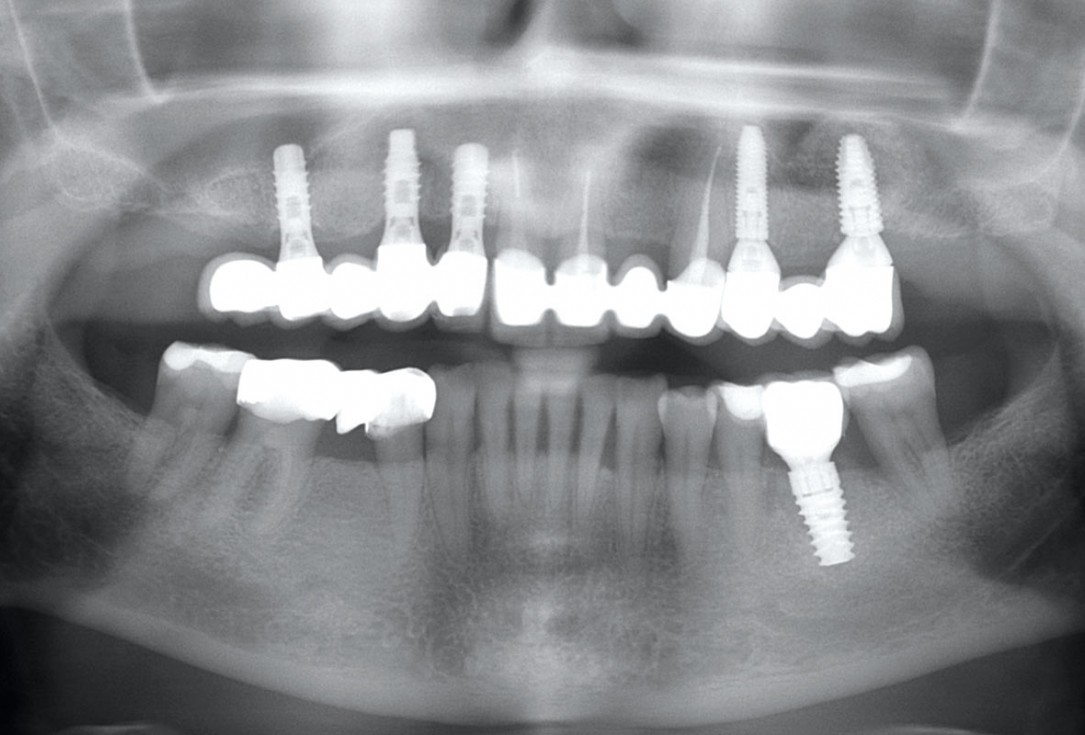

Pre-operative x-ray image, teeth 43, 44, 45, 46 and 47 planned for extraction